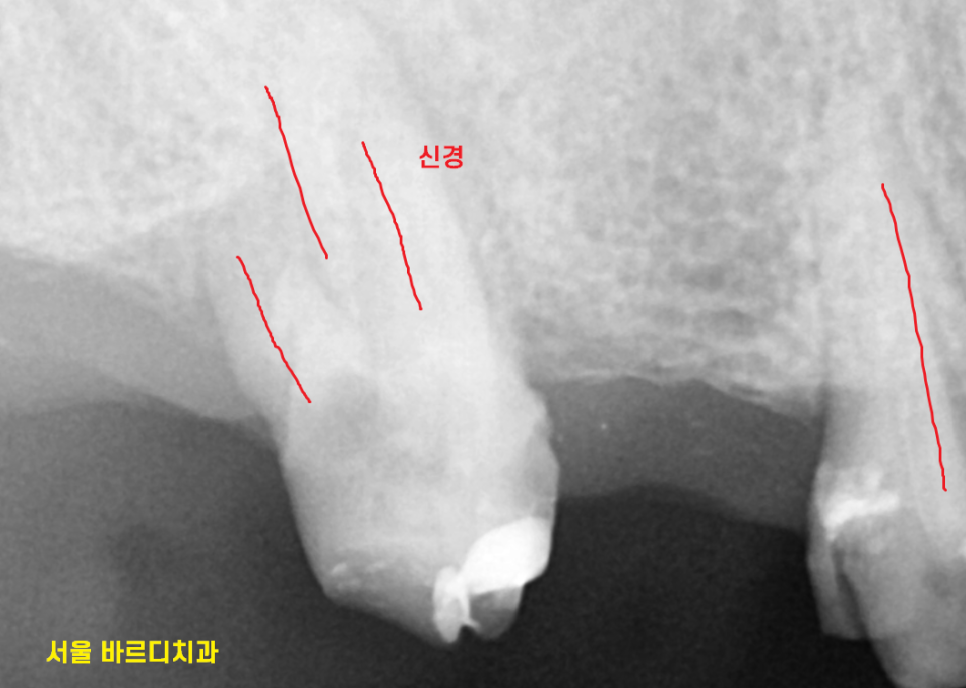

문제의 치아 입니다.

묶어있는 형태였는데요.

23.10.10

아직 반대편 치료가 다 끝나지 않았는데

기존 보철이 빠져버렸네요ㅠㅠ

한눈에 보기에도 상태가 좋지 않죠~?

치아 내부에 충치가 심하고

푸석거려서

살리기 어렵다 말씀드렸습니다.

풍산동 치과에서 ct를 찍어보니

뿌리 흡수도 심하고

갈라지는 부분에 뼈도 많이 녹아있었거든요.